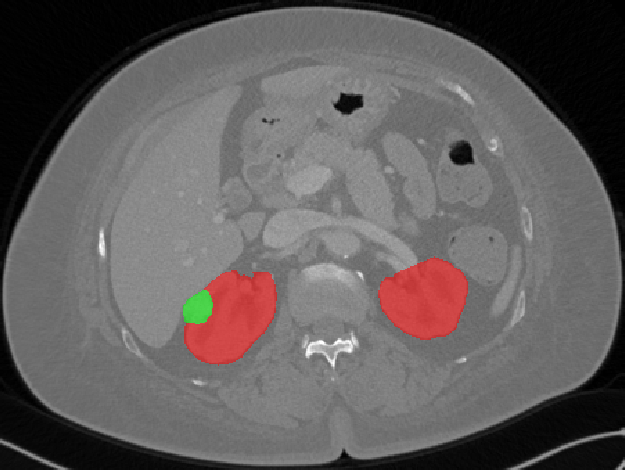

Edge-Aware 3D Image Segmentation Networks

[91]: Automated segmentation of kidneys and kidney tumors is an important step in quantifying the tumor’s morphometrical details to monitor the progression of the disease and accurately compare decisions regarding the kidney tumor treatment. Manual delineation techniques are often tedious, error-prone and require expert knowledge for creating unambiguous representation of kidneys and kidney tumors segmentation. We propose a 3D end-to-end edge-aware FCN for reliable kidney and kidney tumor semantic segmentation from arterial phase abdominal 3D CT scans. Our segmentation network consists of an encoder-decoder architecture that specifically accounts for organ and tumor semantics. We evaluate our model on the 2019 MICCAI KiTS Kidney Tumor Segmentation Challenge dataset. -

Kidney and Kidney Tumor Segmentation

Kidney cancer accounted for nearly 175,000 deaths worldwide in 2018 [13], and it is projected that 14,770 deaths will occur due to the disease in 2019 in the US [111]. Current kidney tumor treatment planning includes Radical Nephrectomy (RN) and Partial Nephrectomy (PN). In RN, both the tumor and the affected kidney are removed whereas in PN the tumor is removed but kidneys are saved [116]. Although RNs were historically prevalent as a standard treatment procedure for kidney tumors, new capabilities for earlier detection of the tumors as well as advancements in surgery has made PNs a viable treatment approach [53].

Traditionally, various techniques such as deformable models [86], GrabCuts, region growing and atlas-based methods have been applied to the problem of kidney segmentation. In recent years, researchers have attempted to leverage the power of deep learning and CNNs to build segmentation frameworks that are more automated and less dependant on incorporation of prior shape statistics. Thong et al. [119] proposed a 2D patch-based approach for kidney segmentation in contrast-enhanced CT scans by leveraging a modified ConvNet.

Jackson et al. [62] developed a framework for detection and segmentation and of kidneys in non-contrast CT images by utilizing a 3D U-Net. Yang et al. [128] proposed a method for kidney and renal tumor segmentation in CT angiography images by a modified residual FCN that is equipped with a pyramid pooling module. Furthermore, Yin et al. [130] employed a cascaded approach for segmentation of kidneys with renal cell carcinoma by training a CNN that predicts a bounding box around the kidney and a subsequent CNN that segments the kidneys. Recently, Xia et al. [126] proposed a two-stage approach for the segmentation of kidney and space-occupying lesion areas by using SCNN and ResNet for image retrieval and SIFT-flow and MRF for smoothing and pixel matching.